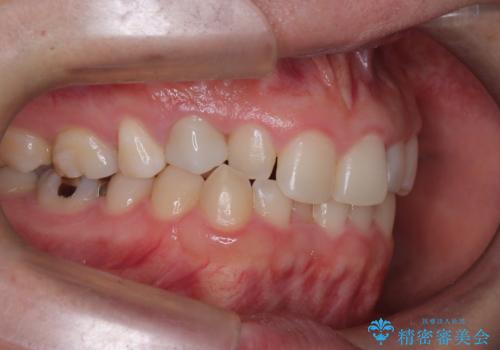

前歯のガタつきと逆の噛み合わせを、短期間のインビザラインで改善

- 前歯の叢生(ガタつき)と、上下の噛み合わせが一部逆になっている反対咬合を主訴にご来院されました。精密検査の結果、前歯の移動だけでは不十分で、歯列全体のアーチを整えながらスペースを確保する必要があると診断。

中等度の症例に最適で最大26ステージ(※プランによる)のマウスピースが使用可能な**「インビザライン・モデレート」**を選択しました。これにより、抜歯をせずに歯列を横に広げ(側方拡大)、前歯を並べる十分なスペースを作りながら反対咬合を確実に改善する計画を立案しました。

反対咬合の解消: 内側に入っていた前歯を、マウスピースの力を利用して外側へ押し出しました。同時に、下顎の歯並びも微調整することで、スムーズに正常な噛み合わせへと誘導しました。